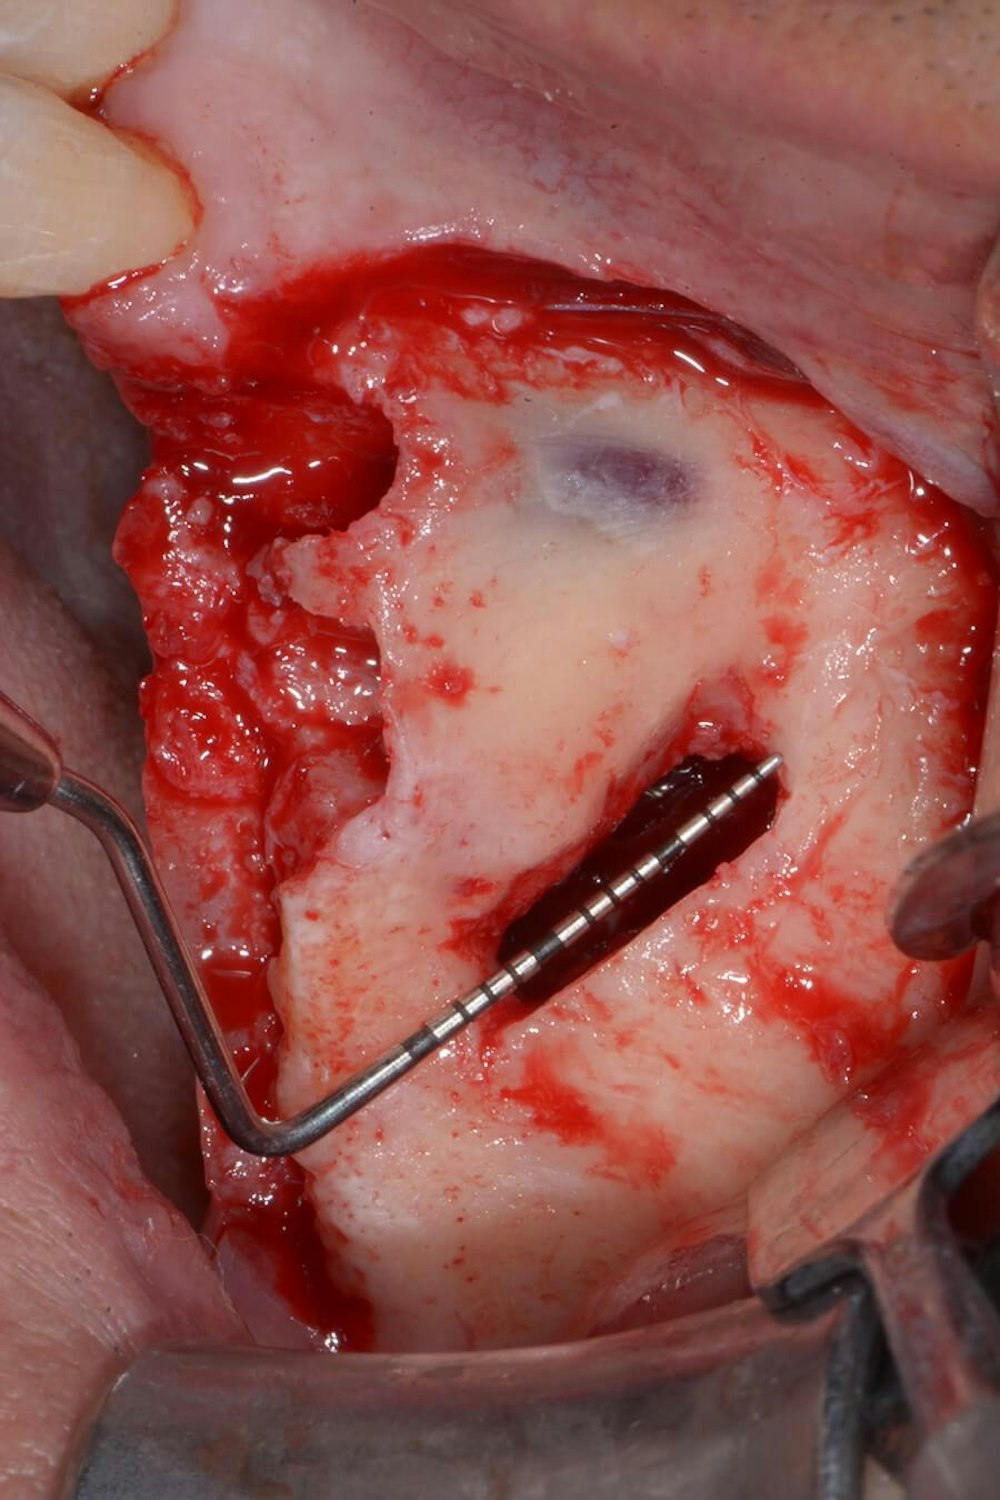

An incision is made along the crest with vertical releasing incisions to obtain access to the lateral and anterior walls of the sinus. The extension of the flap is smaller than a traditional sinus elevation. Once a full-thickness flap is elevated, a small antrostomy is made parallel to the anterior sinus wall starting 3 mm distal to it and then extending anteriorly to reach the anterior sinus wall. The antrostomy is usually 4 to 6 mm mesiodistally and 7 to 8 mm apicocoronally. This simplified antrostomy design is preferred because extension of the antrostomy to the anterior wall renders the membrane elevation procedure simpler and safer by providing direct visual access to the narrow anterior portion of the sinus. This results in a reduced membrane perforation rate (Fig 2a-b).

The antrostomy is parallel to the anterior sinus wall. The membrane has been distally displaced and the nasal mucosa is gently elevated to allow implant site preparation.

Distal displacement of the sinus membrane allows for the placement of an implant with a distal tilt of 30 degrees (Fig. 3). The direction of the first implant drill can be observed through the antrostomy. The preparation of the implant site extends apically through the anterior sinus wall into the cortical layer of the often adjoining lateral nasal wall. After verification of the implant axis using direction indicators, the drilling sequence is finalized and a bone substitute is inserted (on average, 1 mL of graft material is needed). The implant is then inserted through the residual crestal bone into the grafted sinus where the membrane has been previously displaced distally. It engages apically at the M point, the confluence of three cortical walls. In some cases, it may be possible to obtain satisfactory implant stability without engaging the lateral nasal wall cortex. This approach further simplifies the surgical procedure.

The implant drill is used at a 30 degree angle.